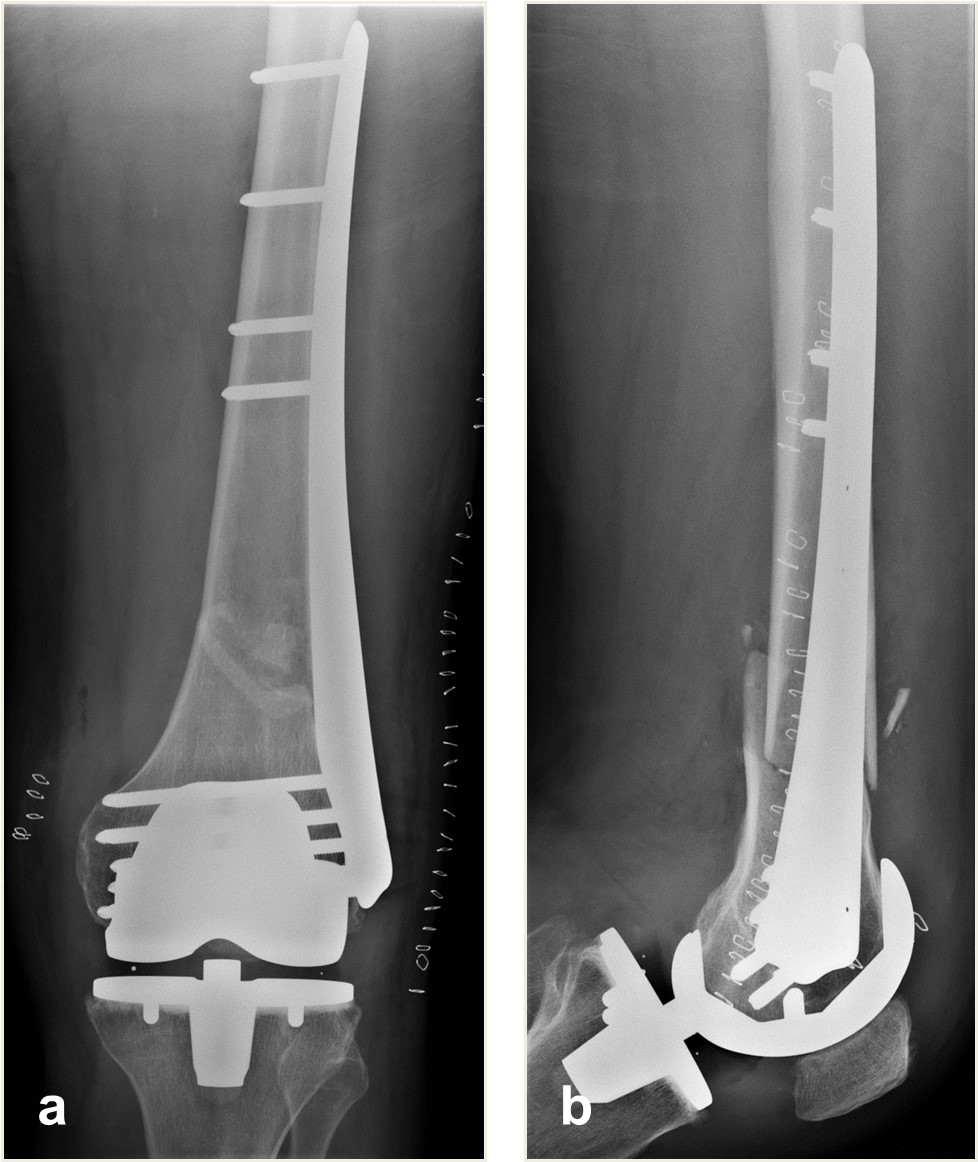

A 64-year-old man was involved in a car injury and sustained a complex floating knee injury with a comminuted distal femoral fracture and a proximal tibial fracture on the left side among various other fractures (Fig 5).

The distal femoral fracture was fixed 3 weeks after injury with ORIF and a Biphasic Plate DF (Fig 6).

The patient healed and returned to preoperative function (Fig 7).